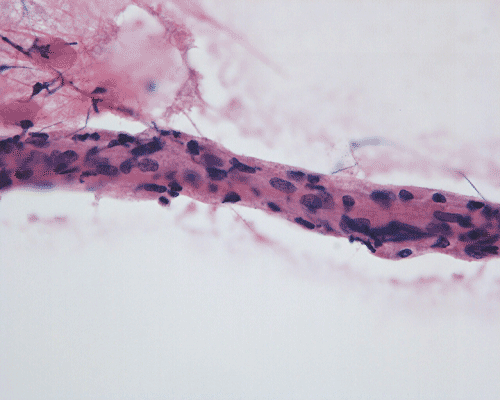

Panel A to E are MR images. Panel F and G are taken from intraoperative cytologic preparation. Panel H to M are taken from frozen section. Panel N and O are from paraffin section. These sections are stained by hematoxylin-eosin stain. Panel P is immunohistochemistry for neurofilament proteins. Panel Q is stained by Luxol fast blue-Periodic acid Schiff (LFB-PAS) stain.

Pathology:

| DIAGNOSIS: Eosinophilic myelitis. |

Pathology of eosinophilic myelitis

Eosinophilic myelitis is featured by lymphocytic infiltration accompanied by a varying intensity of eosinophils. Both the myelin and axons may be damaged. Axonal spheroids can be seen and indicate primary axonal damage rather than secondary damage following demyelination 14, 15. Destruction of axons in the lesion may well explain the relatively poor recovery of this condition. There is increase in eosinophils in CSF in the our under discussion. However, the CSF studies are normal in two previous studies 14, 15.

The eosinophils play an important role in causing the damages. Infiltration by eosinophils and depositions of activated products of eosinophils are commonly seen in atopic disorders, such as atopic bronchial asthma, allergic rhinitis and atopic dermatitis. The presence of atopic diathesis as well as eosinophilic cationic protein deposition suggests that atopy may represent one of the risk factors for developing eosinophilic myelitis. Eosinophilic cationic protein is one of the neurotoxic proteins released by activated eosinophils Eosinophil cationic protein and other products of eosinophils such as major basic protein have been shown to be neurotoxic. The infiltrating eosinophils may therefore well contribute to the neural damage.